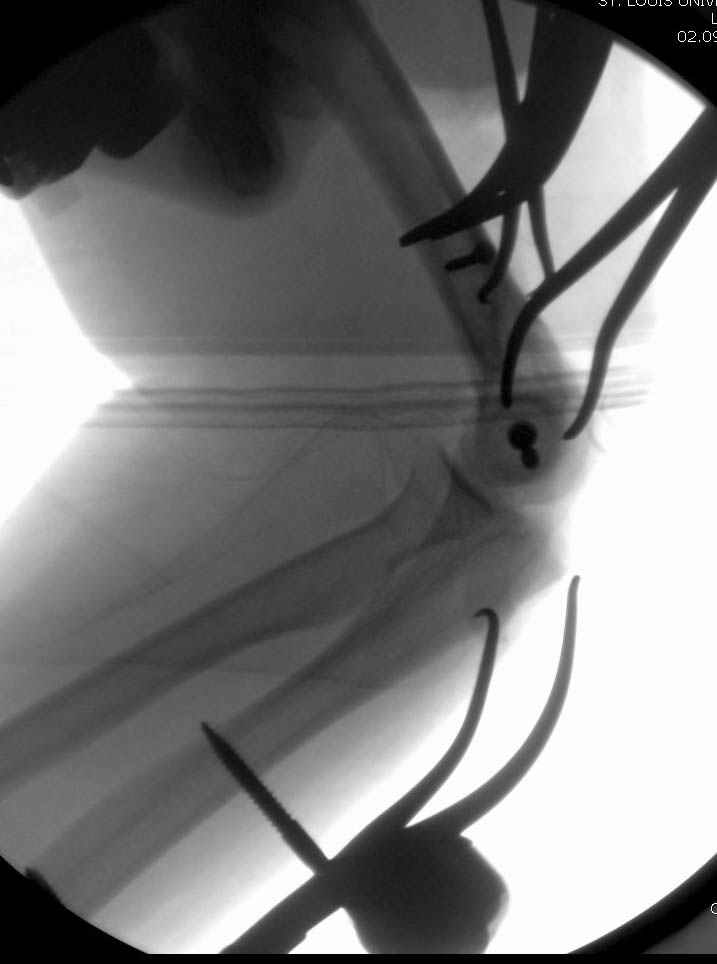

Примерный случай, только перелом был открытый, в задне-медиальной стороне рана около 2 см по характеру "изнутри кнаружи", неврологический статус со слабостью сгибания мизинца, также слабая абдукция и аддукция указательного пальца и сгибания в кисти.

Больному сделали обработку и наложили временный аппарат внешной фиксации плечо-предплечье.

На шестой день сделали открытую репозицию чрезлоктевым доступом двумя locking plate, локтевой нерв был ушибленным, после операции положительная динамика в Flexor Carpi Ulnaris. Фиксацию локтевого отростка произвели tension band technique с дополнительным шурупом.

Этапы операции на снимках....

Джолдас Кульджанов

Djoldas Kuldjanov, MD

Department of Orthopedic Surgery

St. Louis University Medical Center